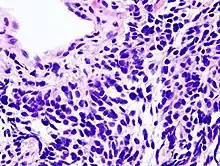

Overordnet opdeler man lungekræft i to typer: småcellet og ikke-småcellet. Denne opdeling baseres på, hvordan de maligne celler ser ud ved mikroskopi. Ca. 20 procent af alle tilfælde af lungekræft vil være af den småcellet type og ca. 80 procent vil være af den ikke-småcellet type. Opdelingen er set ud fra et behandlingssynspunkt vigtig, da den småcellet type er mere følsom for kemoterapi end den ikke-småcellet type.

Småcellet lungekræft, også kaldt "oat cell lung cancer" (på engelsk "havregryns"-kræft), fordi cellerne under et mikroskop er meget små og kan ligne havregryn af udseende.[7] Småcellet lungekræft ses hos lidt under 15 procent af de lungekræftramte og denne type lungekræft forkortes ofte SCLC. Denne type lungekræft opstår i som oftest i de større bronkier i lungerne og udgår fra endokrine celler. Småcellet lungekræft er væsentlig mere aggressiv end den ikke-småcellet, og personer med denne type vil have en dårligere prognose end personer med den ikke-småcellet type.